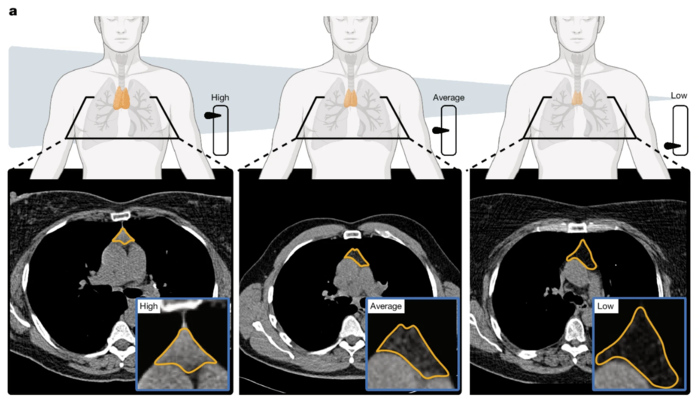

▲ a. 흉선 건강의 그림. 흉선 기능의 영상 기반 지표와 흉선 건강이 높음, 평균, 낮음인 세 명의 대표적인 사례를 보여준다. 흉선 부위는 주황색으로 표시되어 있다. (출처:Published: 18 March 2026 / Thymic health consequences in adults)

연구진은 먼저 컴퓨터 단층 촬영(CT)을 이용해 연구 대상자들의 흉선 크기, 모양, 상태를 측정했다. 이를 바탕으로 흉선 건강 지수를 개발했다. 이 지수는 흉선 위축 속도가 개인마다 다르다는 것을 보여주었다. 흉선의 상태는 나이뿐만 아니라 과체중이나 흡연과 같은 생활 습관 요인에도 영향을 받는다. 여성의 경우, 흉선 퇴화 속도는 남성보다 평균적으로 더 느리다.